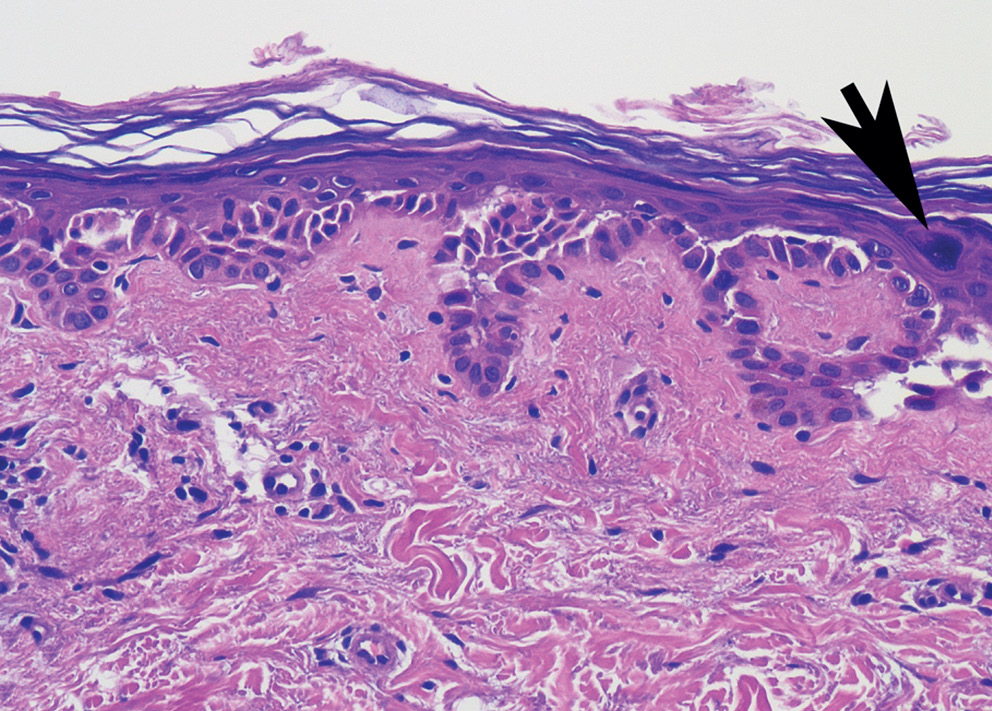

При гистологическом исследовании болезни Гровера наиболее часто встречающимся морфологическим вариантом является Дарье-подобный, который характеризуется наличием акантолиза с явлениями дискератоза в виде образования так называемых «круг- лых телец» и «зерен» в эпидермисе (рис. 4). Другие гистологические варианты заболевания включают спонгиотический, пемфигус-подобный (обычно гистологическая картина при данном варианте имеет сходства с вульгарной/листовидной пузырчаткой) и Хейли–Хейли-подобный [2] (рис. 5, 6). Спонгиотический вариант характеризуется наличием спонгиотической внутриэпидермальной полости, пемфигус-подобный — акантолизом на разных уровнях эпидермиса, Хейли–Хейли-подобный — гиперплазией эпидермиса с явлениями акантолиза в виде «рушащейся кирпичной стены». Разные гистологические варианты заболевания могут сочетаться у одного пациента (рис. 7).

Рис. 5. Пемфигус-подобный вариант болезни Гровера: супрабазальный акантолиз с образованием щелей в эпидермисе. Видна крупная дикератотичная клетка (стрелка)

Fig. 5. Pemphigus-like variant of Grover’s disease: suprabasal acantholysis with the formation of cracks in the epidermis. A large diceratotic cell is visible (arrow)